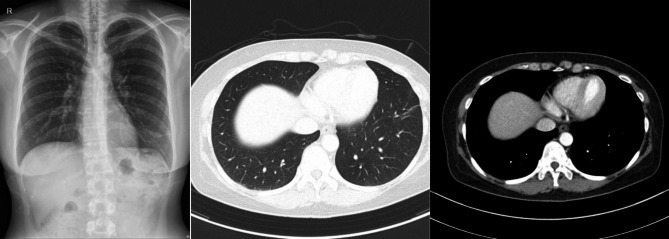

Case presentation: A 46-year-old healthy woman was incidentally found to have a 1.3-cm pulmonary nodule in the left anterior basal segment during a routine health examination, with no symptoms or significant medical history. Initial CT imaging raised suspicions of T1a lung cancer. Subsequent endobronchial ultrasound transbronchial lung biopsy and transbronchial lung cryobiopsy revealed granulomatous inflammation. Tests for tuberculosis and NTM, including acid-fast bacilli (AFB) smear, mycobacterial culture, and PCR for Mycobacterium tuberculosis and NTM, were negative. Following the biopsies, chest X-rays showed an enlarged shadow at the lesion, suggesting necrosis after cryobiopsy. The patient was treated with moxifloxacin, leading to symptom improvement. A final diagnosis of NTM infection, specifically Mycobacterium avium, was confirmed from bronchoalveolar lavage fluid obtained three weeks after the tissue biopsy. Remarkably, at four months post-biopsy, a chest CT scan showed complete resolution of the nodule without additional antimicrobial therapy, suggesting a potential therapeutic effect of cryobiopsy-induced cryoablation.